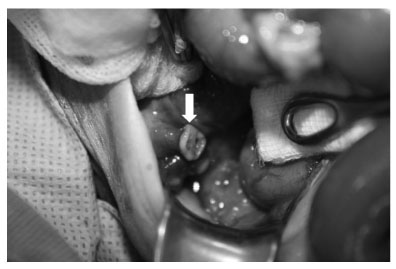

Abdominal exploration shows the appendix completely transected (arrow).

Fig. 2 Abdominal exploration shows the appendix completely transected (arrow).